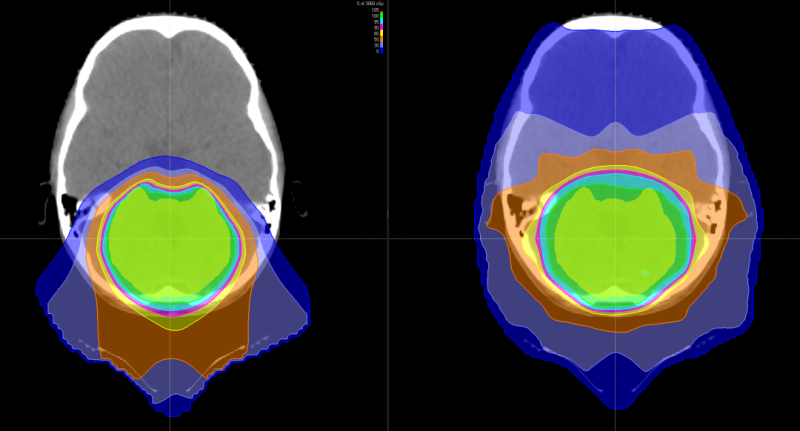

上图为髓母细胞瘤对全脑全脊髓照射剂量的分布图比较,传统放疗会对身体造成大范围的损害,波及脊柱周边的脏器,而质子治疗剂量分布图,脊髓周边的照射剂量机乎为零,不会造成损害及副作用。